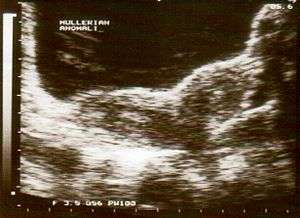

| Ultrasound showing didelphys | |

Uterus didelphys (sometimes also uterus didelphis) represents a uterine malformation where the uterus is present as a paired organ when the embryogenetic fusion of the Müllerian ducts fails to occur. As a result, there is a double uterus with two separate cervices, and rarely a double vagina as well. Each uterus has a single horn linked to the ipsilateral fallopian tube that faces its ovary.

Helpful techniques to investigate the uterine structure are transvaginal ultrasonography and sonohysterography, hysterosalpingography, MRI, and hysteroscopy. More recently 3-D ultrasonography has been advocated as an excellent non-invasive method to evaluate uterine malformations.[3]